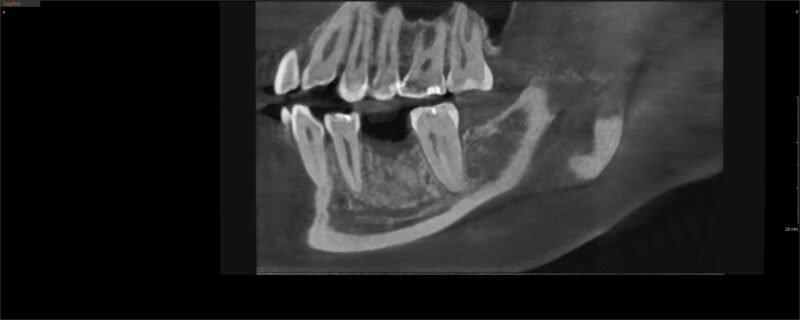

I can definitely see the dimensional changes you mentioned, but the bone inside the socket looks how I would expect it to look.

What I do see that is missing though is a nice cortical shell formation at the top of the socket. If you wait longer, sure, you will get a better cortical plate formation for you to feel more comfortable placing your implant. But I think it is also totally possible to place an implant as is.

As far as size selection, I would be comfortable with a 4-4.5 mm width and a 8mm length. The position of your ruler over the site is not exactly on the bone (the lines extend out a little bit) so I would rather be a bit more conservative.